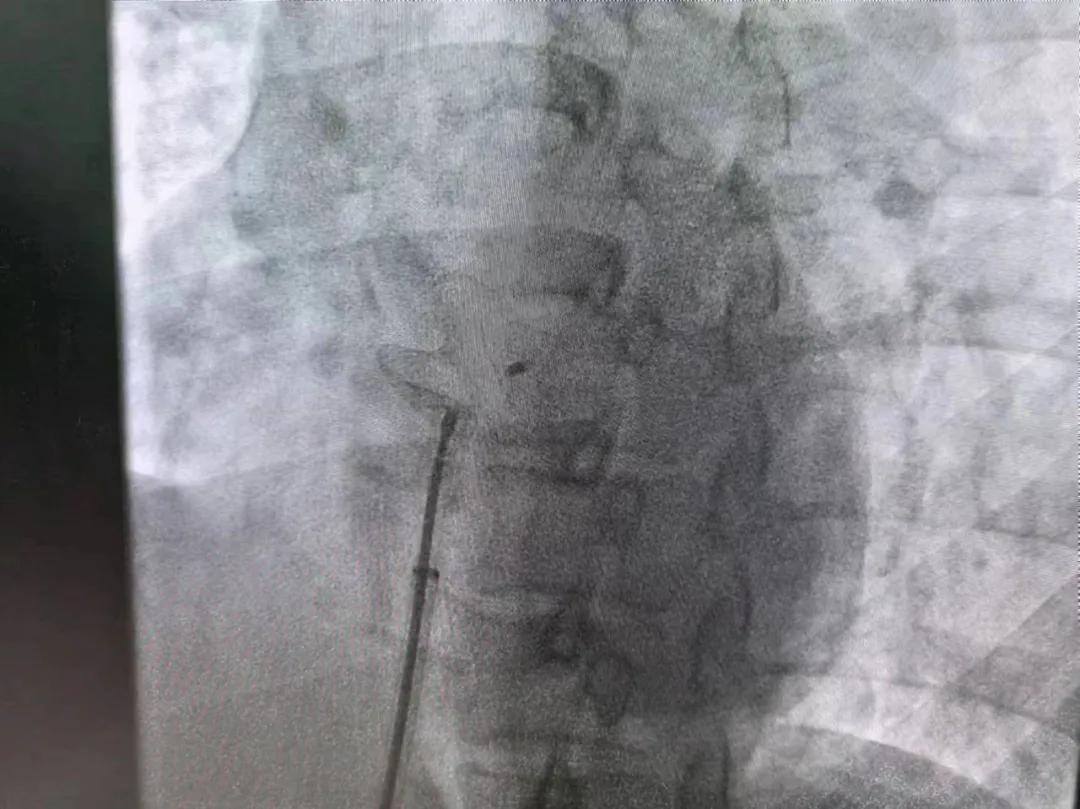

繼3月14日市二院成功開展首例卵圓孔未閉介入封堵術之后,3月21日上午,市二院院長王瑾及心血管內(nèi)科主任李慧新帶領心血管內(nèi)科介入團隊,再次成功為患者實施“經(jīng)皮房間隔缺損封堵術”,手術過程順利。該例病人的成功手術及康復,標志著市二院心血管內(nèi)科在結構性心臟病介入診療中再次達到了新高度。

患者為中年女性,41歲,近2年一直反復出現(xiàn)頭暈、頭痛,曾先后在多家醫(yī)院就診。近期患者癥狀加重,出現(xiàn)活動后氣喘合并胸悶癥狀,來到心血管內(nèi)科就診。經(jīng)心臟彩超檢查顯示:患者房間隔下段連續(xù)性中斷,缺損直徑達到了13mm,肺動脈壓已經(jīng)輕度增高,確診為房間隔缺損。

于是,院長王瑾會診后,詳細詢問患者病史,認真分析臨床癥候群并準確診斷,耐心做好患者及家屬病情告知和充分溝通。經(jīng)過完善的術前評估及準備,心血管內(nèi)科介入團隊成功為患者實施“經(jīng)皮房間隔缺損封堵術”,手術過程順利。近日,患者已順利康復出院。 (尹紅婭 潘長林)